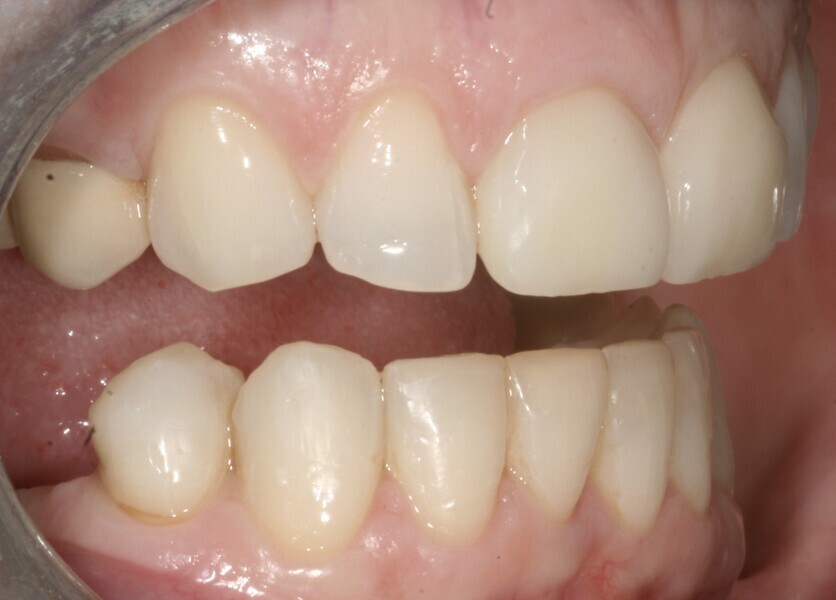

A 48-year-old female patient came to see me in 2004. The patient initially presented because she was unhappy with her two discoloured maxillary central incisors (Fig. 1). She also had chipping and wear of the mandibular teeth and broken posterior bridgework. Her “bite” also felt uncomfortable (Fig. 2).

On examination, she had reduced anterior guidance, causing posterior interferences and heavy contacts behind the maxillary central incisors. The patient was keen to change the crown and veneer on the maxillary central incisors. She also wanted to have the wear on her mandibular teeth and the crowding treated (Fig. 3).

Fig. 2: 2004—reduced anterior guidance.

Fig. 3: 2004—wear on the mandibular teeth and crowding.